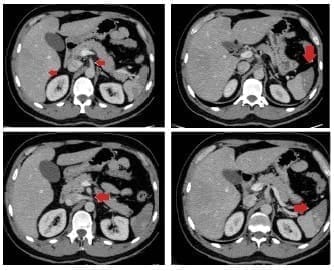

Por la persistencia del dolor se solicitó una tomografía computarizada contrastada de abdomen para descartar patología inflamatoria, encontrando múltiples infartos esplénicos y trastorno de la perfusión hepática, con aparente origen en un defecto de llenado lineal del tronco celíaco (figura 1).

Figura 1. Tomografía computarizada abdominal con contraste venoso. Se observan múltiples infartos esplénicos y trastorno de la perfusión hepática que tienen aparente origen en un defecto de llenado lineal del tronco celíaco (flechas).